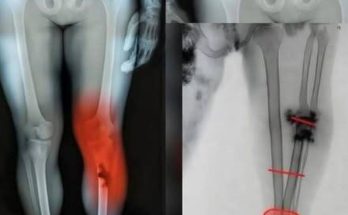

Kaleb was born with Osteogenesis Imperfecta, a condition that causes bones to break very easily. Because of this disorder, even small movements or minor accidents can result in fractures. Throughout his young life, Kaleb experienced more than 200 bone fractures, a number that reflects just how difficult his journey truly was.

Communities online have also used this moment to spread awareness about osteogenesis imperfecta. The condition is rare, but organizations like Shriners Children’s continue working to provide treatment, research, and support for affected families. Kaleb’s story has helped bring attention to the challenges these children face and the importance of specialized care.